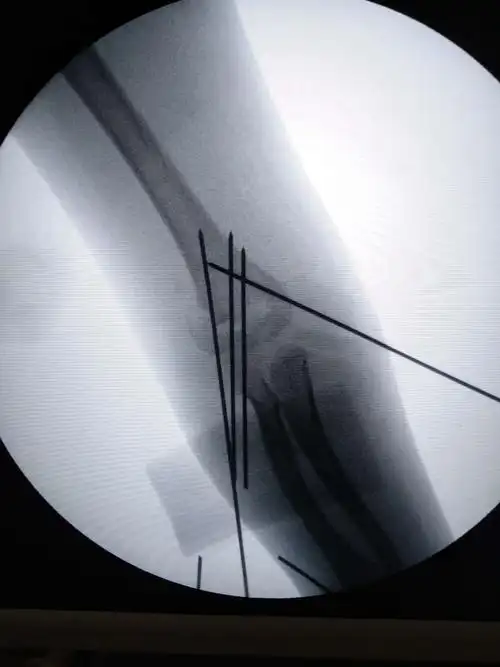

刘道禹肱骨髁上骨折